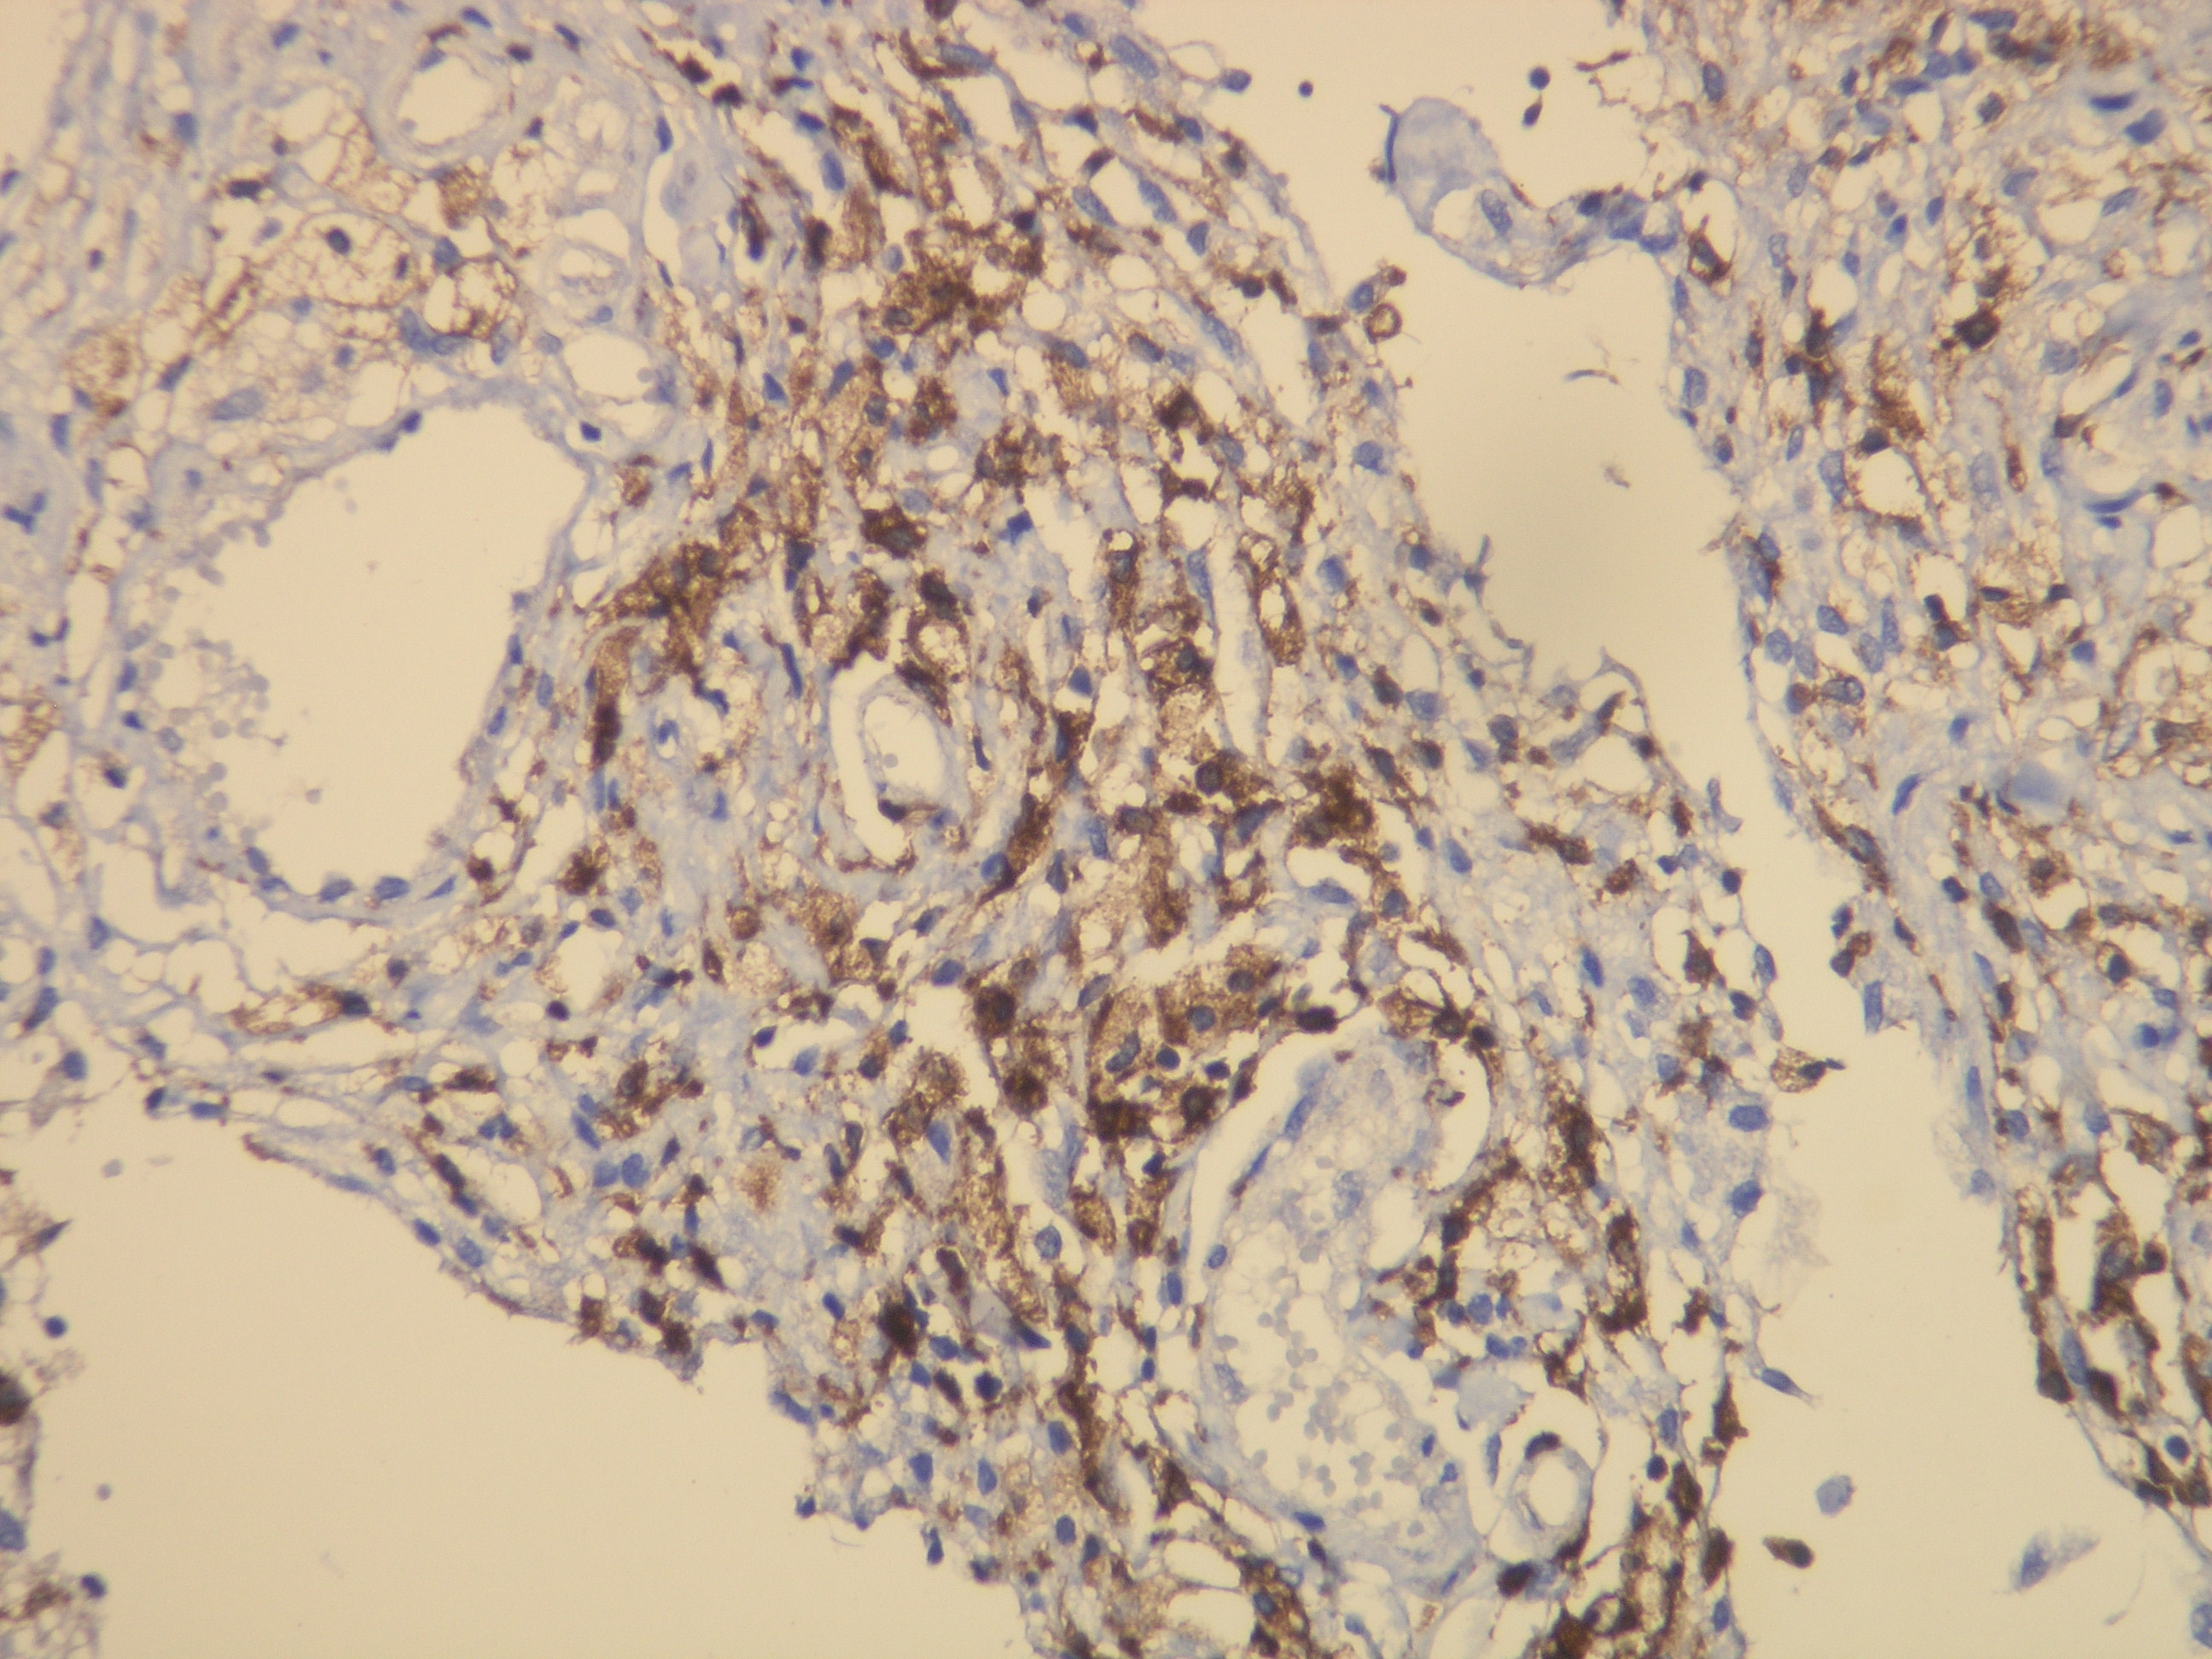

Anti-CD163

Kód produktu:DB 045 Kategória:IHC-P

Peptid derivovaný z N-koncovej sekvencie ľudskej CD163. Protilátka rozpoznáva epitop umiestnený medzi Gly134 - Gly148.

Aplikácia

IHC-P, riedenie 1:100

db045 db045b db045c